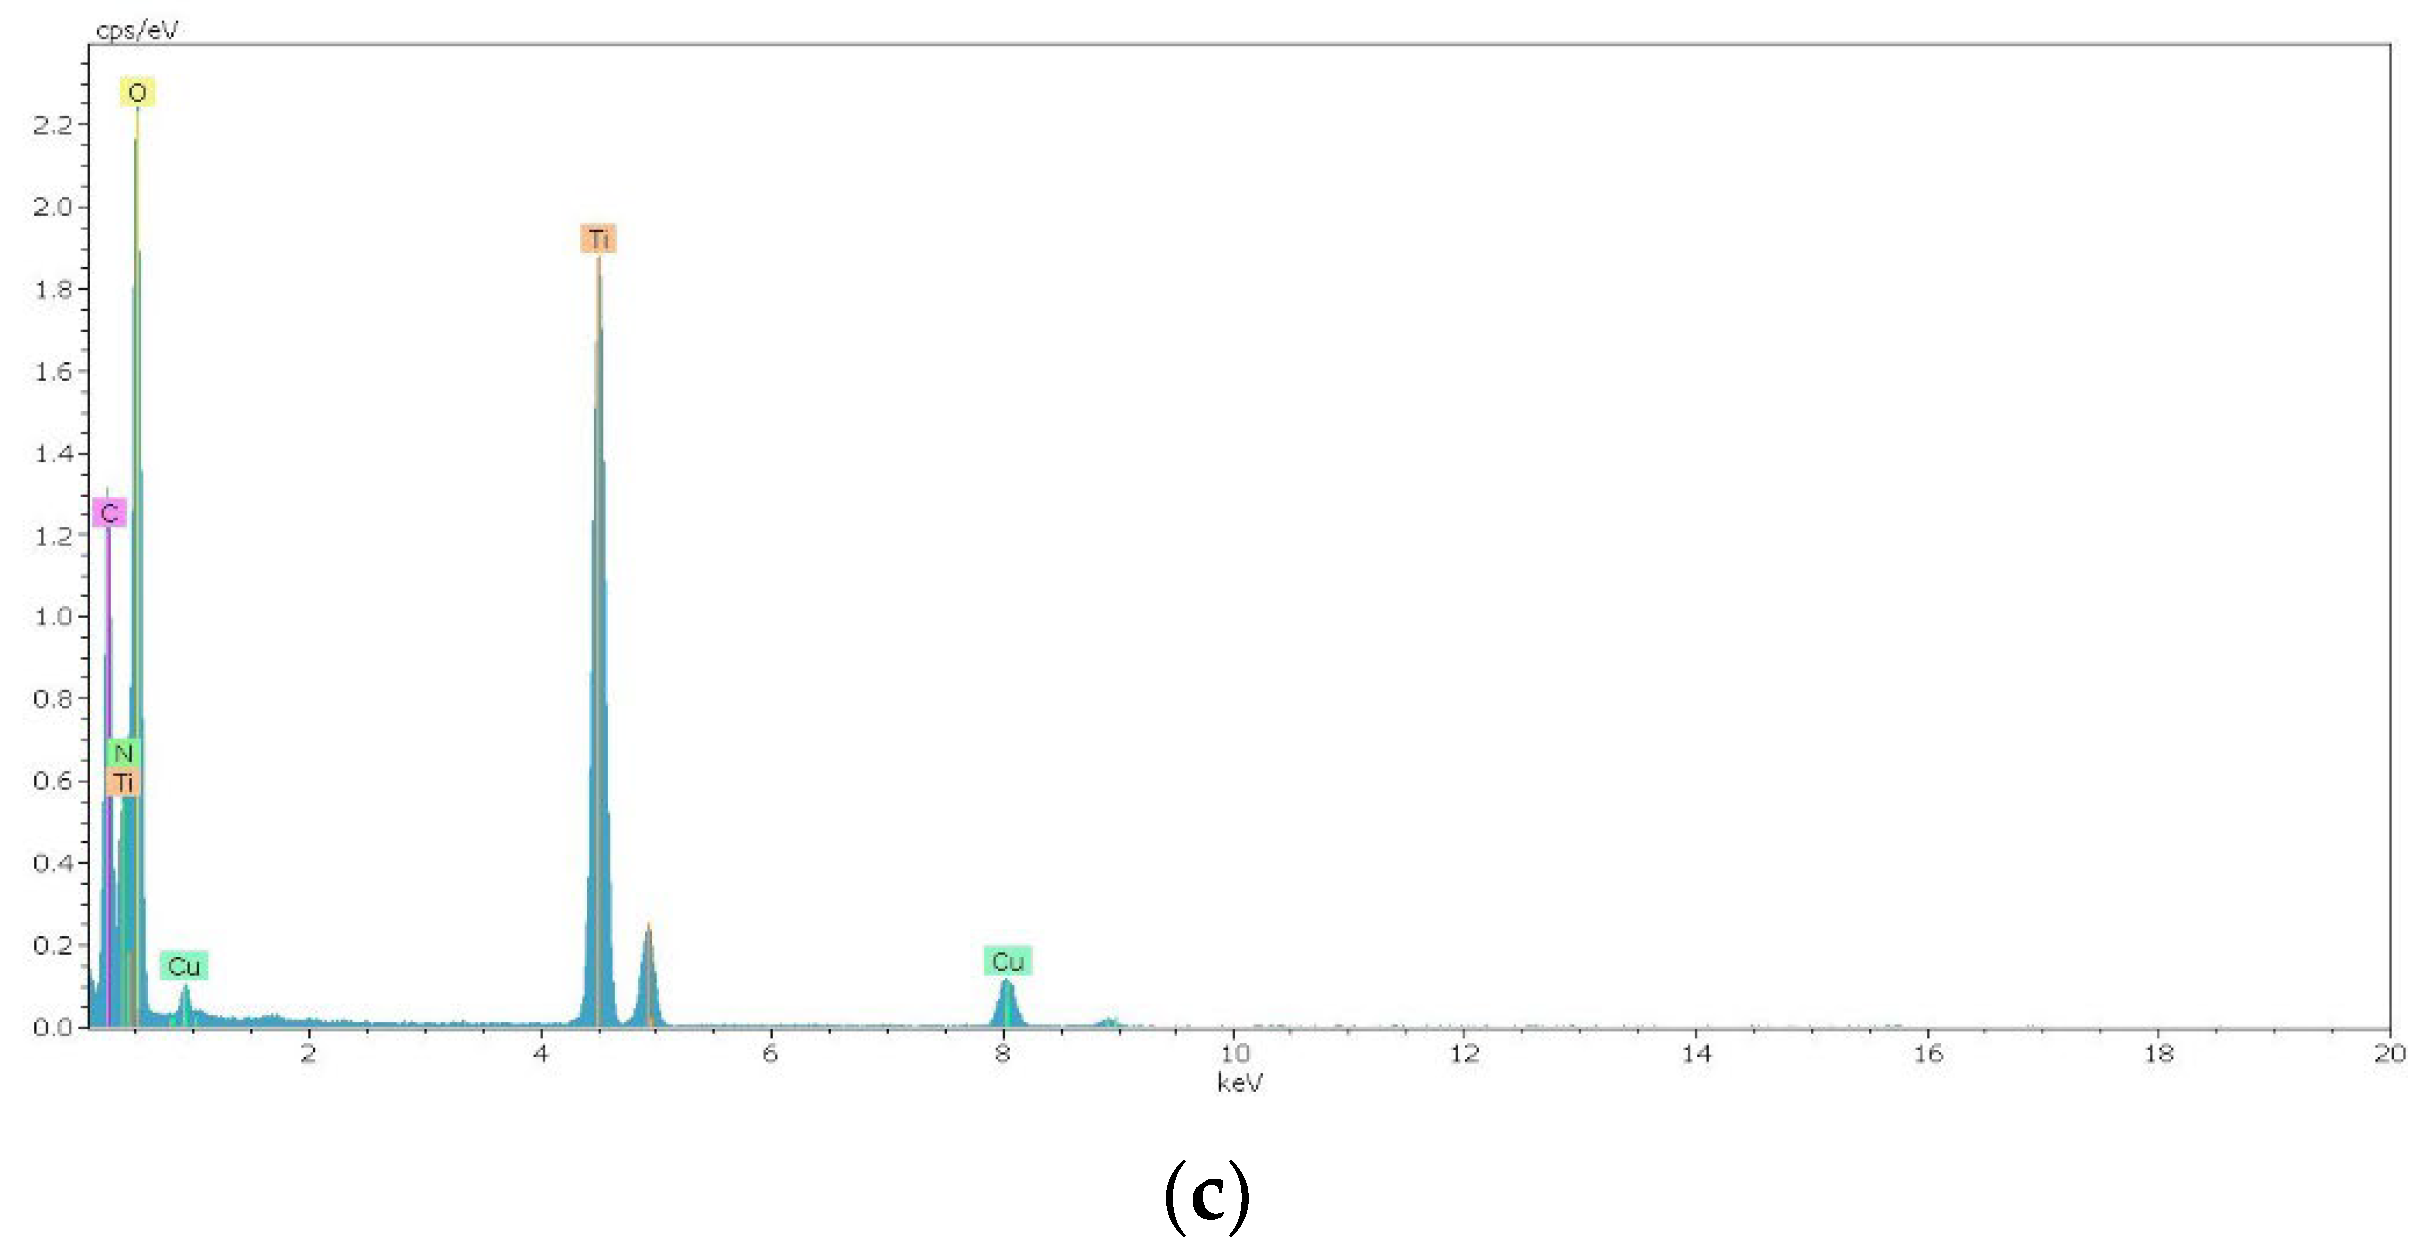

4.4. Methods of Scanning Electron Microscopy (SEM) and Transmission Electron Microscopy (TEM) with Energy Dispersive (ED) Analysis

2.1.1. Results of X-ray and Electron Microscopic Studies